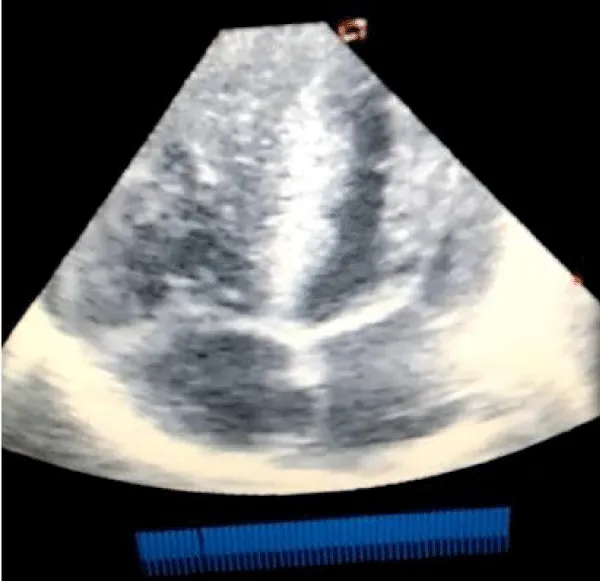

A male neonate delivered at term via SVD to a 24 years old G2P2 mother, who was diagnosed with gestational diabetes at 31 weeks of gestation who had poor glycemic control despite being on subcutaneous insulin and dietary modifications. Mother also had gestational diabetics during her first pregnancy (deranged glycated haemoglobin HbA1c) and claimed her blood sugar normalized after delivery. Her first child was a female and weighed 4.5 kg, alive and well and did not have any immediate neonatal complications. No family history of cardiac diseases. Birth weight of index baby was 4.8 kg (> 95% centile for age) and Apgar scores were 5/7/7 in 1, 5 and 10 minutes respectively. The physical examination showed a macrosomic infant (weight > 95% centile for age), thick upper extremity skin folds, broad shoulder and torso with a relatively smaller head, and plethoric look. He had respiratory distress with peripheral cyanosis. Oxygen saturation (SPO2) was 92% (room air) and urgent random blood sugar (RBS) was 4.6mmol/l. There were no other obvious malformations. Baby was admitted immediately after birth into the special care baby unit (SCBU) of a Federal Medical Centre in southern part of Nigeria for moderate birth asphyxia, severe respiratory distress and macrosomia. Child had persistent respiratory distress while on admission and further cardiac evaluation revealed displaced apex beat with no cardiac murmur. Chest x-ray done showed severe cardiomegaly with bi-ventricular and right atrial enlargements and a cardiothoracic ratio of 68% and oligaemia (Figure 1). Electrocardiography showed evidence of biventricular hypertrophy, right atrial enlargement, sinus tachycardia and occasional premature ventricular complexes (Figure 2). Echocardiography done on the 7th day of life showed severe bi-ventricular hypertrophy with significant narrowing of the left ventricular cavity, marked asymmetrical septal hypertrophy, moderate to severe dynamic subaortic stenosis (Peak gradient 45 mmHg) and left ventricular systolic and diastolic dysfunction (Figure 3). He was commenced on tabs propranolol at 1mg/kg/dose 8hrly and discharged after 5 days with improvement in respiratory distress. He also received oxygen therapy, intravenous fluid and intravenous antibiotics as well as intensive nursing care while on admission. Follow up echocardiography at 6 wks of life showed evidence of remarkable resolution of hypertrophy and improvement in ventricular function (Figure 4).

Download Image

Figure 3: Echocardiography (apical 4 chamber view) showing severe biventricular and septal hypertrophy causing left ventricular outflow tract obstruction and a markedly diminished left ventricular cavity.